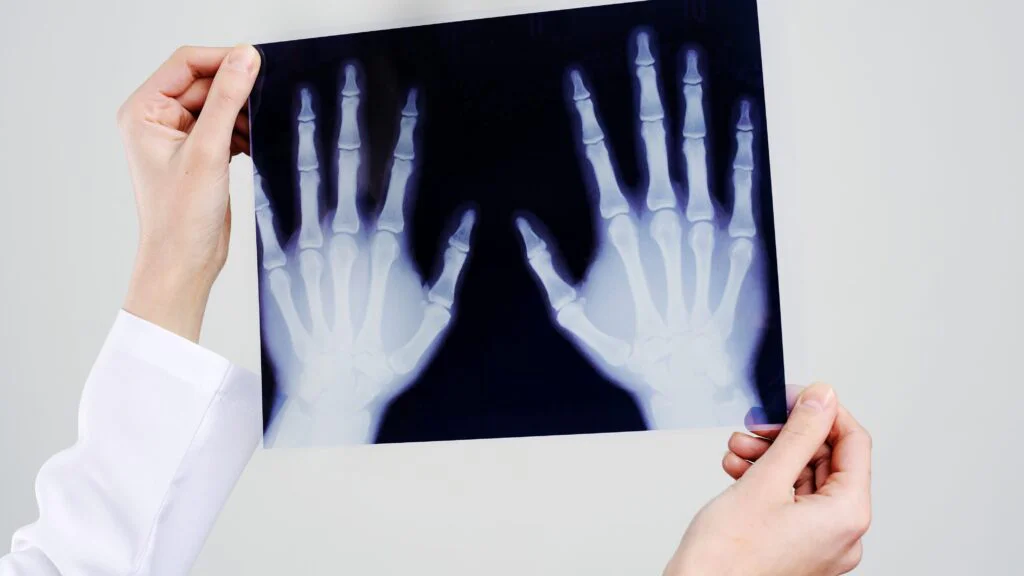

Vynálezy doprovázejí lidstvo po celou dobu jeho existence, neboť umožňují pokrok. Koncem 19. století nastaly obzvlášť přínosné časy, jelikož byla věnována velká pozornost fyzice. Otevřela se tak cesta k mnohem složitějším a převratnějším výzkumům. Jedním z nich byl Röntgenův objev rentgenových paprsků, čímž se výrazně posunula medicína.

Princip, který vedl k zavedení rentgenu, Wilhelm Röntgen objevil náhodou.